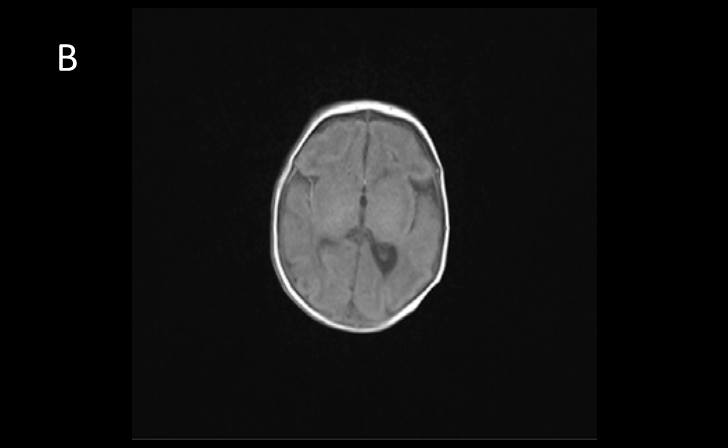

图2. 患儿2月龄时的MRI显示其胼胝体很薄(A),

髓鞘化程度低(B)。